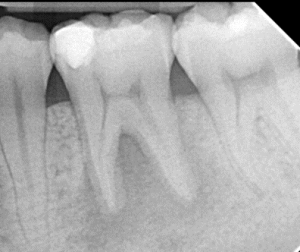

Clinical Cases